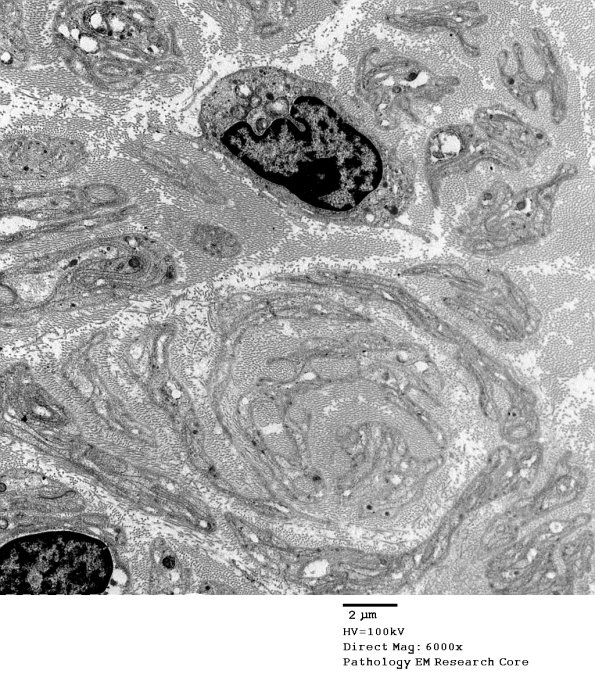

Several examples of the collection of Schwann cell processes consistent with forming pseudo onion-bulbs, structures in which crescentic aggregates of Schwann cell processes and basal lamina mimic onion-bulbs. Whereas true onion-bulbs are evidence of cycles of demyelination/remyelination, pseudo onion-bulbs typically characterize marked loss of axons. (electron micrographs)